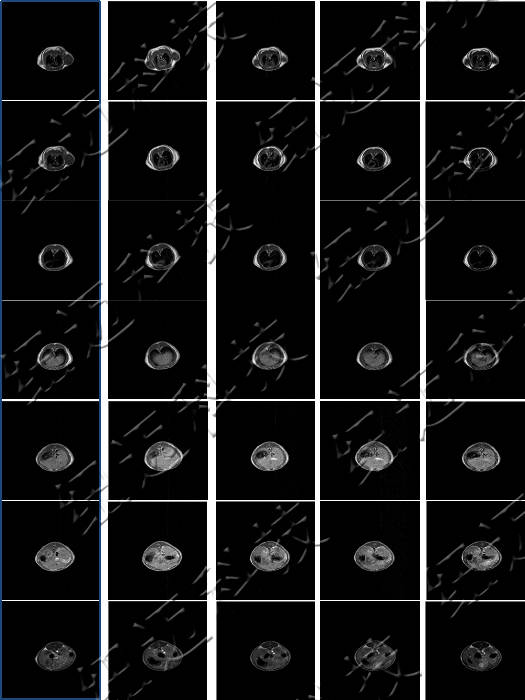

儀器使用小動物核磁共振成像系統,圖像為T1加權像橫斷面、冠狀面,采樣參數如下:FOV=100mm×100mm, TR=400ms, TE=19ms, 層厚3.5mm, 層間距1mm, 累加次數16, K空間大小192×256。成像結果顯示,注射造影劑后,大鼠心臟與肝臟變亮,且隨代謝時間延長逐漸變暗。

大鼠體內造影劑代謝MRI橫斷面